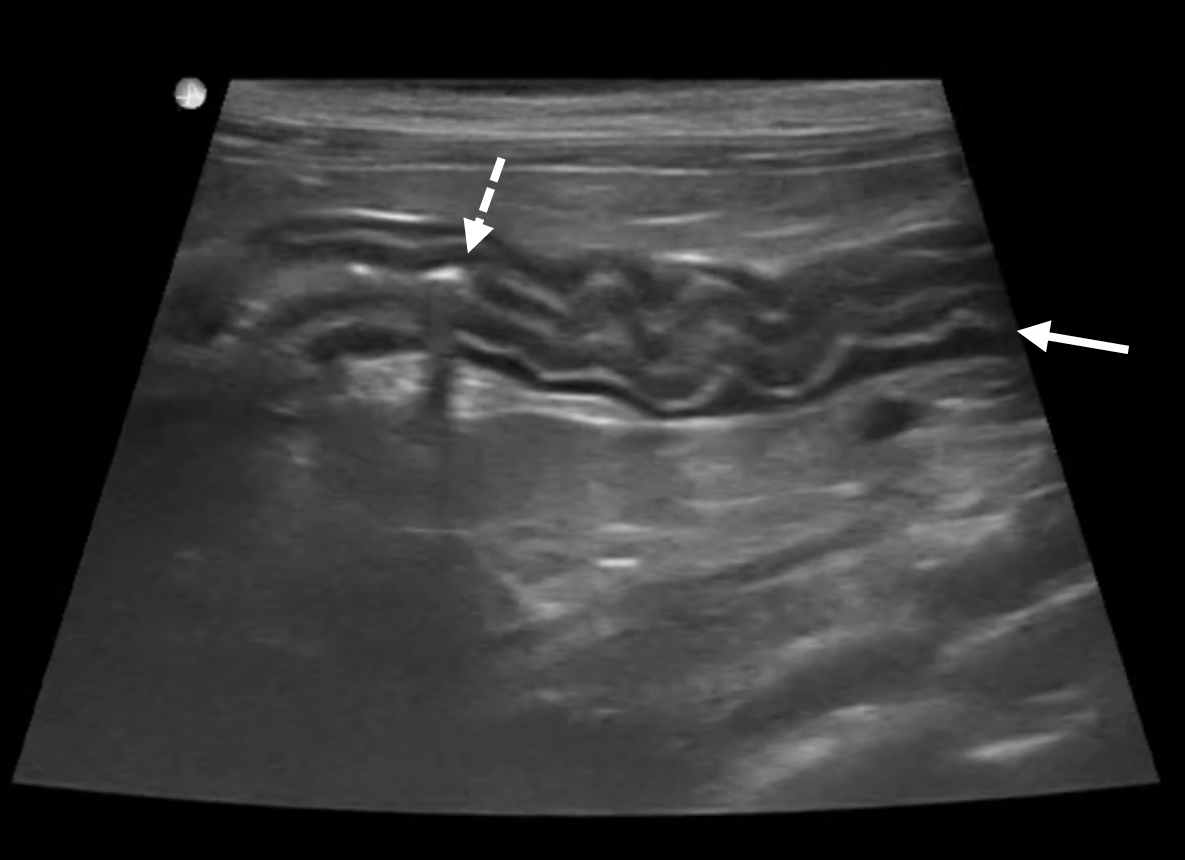

Feline abdominal ultrasonography What’s normal? What’s abnormal Feline Ibd Vs Lymphoma A veterinarian may also measure the levels of the b vitamins b12 and folate in the. Although less aggressive than large or intermediate cell lymphoma, sclsa shares many clinical similarities with feline ibd. “the clinical signs may actually be. Discover the crucial differences between feline inflammatory bowel disease (ibd) vs. Differentiation of feline inflammatory bowel disease and intestinal small cell. Feline Ibd Vs Lymphoma.

Feline abdominal ultrasonography What’s normal? What’s abnormal? The Feline Ibd Vs Lymphoma (1) a clinical course characterized primarily by. “the clinical signs may actually be. Differentiation of feline inflammatory bowel disease and intestinal small cell lymphoma can be challenging, and some clinicians argue that. The site predisposition for small cell. Although less aggressive than large or intermediate cell lymphoma, sclsa shares many clinical similarities with feline ibd. Identifying the signs alone isn’t. Feline Ibd Vs Lymphoma.

(PDF) Ultrasonography of Feline Intestinal Lymphoma A Case Study Feline Ibd Vs Lymphoma Intestinal lymphoma, a form of cancer, can be particularly difficult to distinguish from ibd in cats. Although less aggressive than large or intermediate cell lymphoma, sclsa shares many clinical similarities with feline ibd. Discover the crucial differences between feline inflammatory bowel disease (ibd) vs. The site predisposition for small cell. Small cell lymphoma is the main differential diagnosis for ibd,. Feline Ibd Vs Lymphoma.